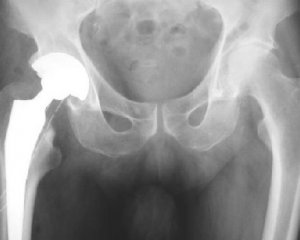

Диагностический процесс при подозрении на деформирующий артроз тазобедренного сустава начинается с рентгенологического исследования. Основные признаки, подтверждающие наличие заболевания, включают:

- сужение пространства между суставными поверхностями костей

- образование остеофитов – костных разрастаний

- постепенное уплощение головки бедра

- обызвествление мягких тканей, окружающих сустав.

На основе результатов рентгенографии устанавливается стадия заболевания. Для первой стадии характерны изменения в структуре кости, уплотнение в подхрящевой области и появление небольших остеофитов по краям суставной поверхности.

Во второй стадии наблюдается сужение суставной щели с более выраженным остеосклерозом. В третьей стадии все изменения усугубляются: краевые остеофиты увеличиваются, а суставная щель становится менее заметной.

На четвертой стадии суставная щель практически полностью исчезает, а эпифизарные концы костей приобретают резко изменённую форму. Кроме рентгенологического исследования, в диагностическую программу должны быть включены следующие анализы: